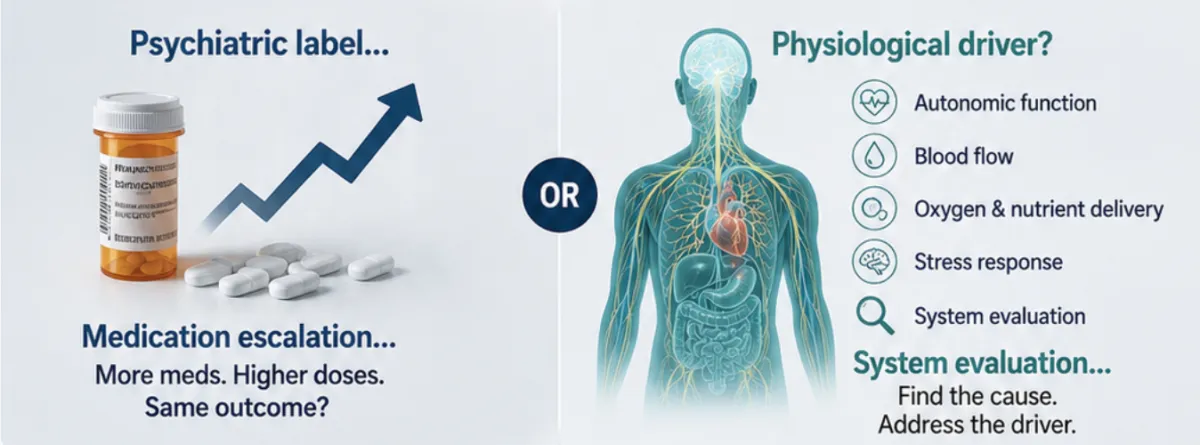

The Clinical ImplicationS

This raises a critical question for providers:

If the underlying issue is dysregulation… can symptom-based treatment alone resolve it?

Without assessing autonomic function, clinicians may be:

Treating downstream symptoms

Missing upstream dysfunction

Escalating treatment without identifying cause

The Opportunity for Precision

The Brain Medicine findings highlight that autonomic dysfunction is measurable, identifiable, and clinically relevant in a subset of patients with persistent depressive symptoms.

When treatment isn’t working, the next step matters.

Not every case is purely chemical.

Not every non-response is resistance.

Not every solution is more medication.

REFRAME THE DECISION

Not every case is purely chemical.

Not every non-response is resistance.

Not every solution is more medication.